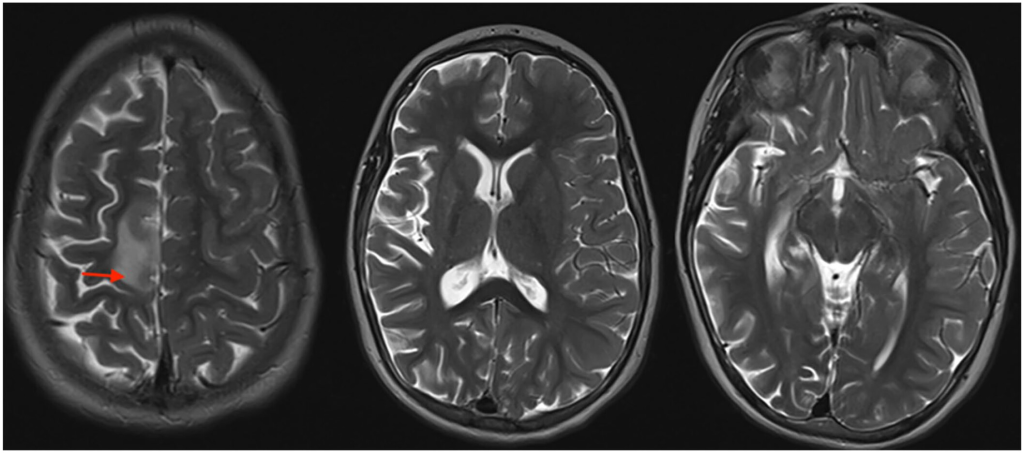

- Unilateral Brain Atrophy: MRI scans revealing shrinkage and scarring in one cerebral hemisphere, which worsens over time.

6. How is RE diagnosed?

Diagnosis is based on clinical symptoms (seizures, hemiparesis), EEG showing unilateral abnormalities, and MRI showing progressive atrophy of one hemisphere.